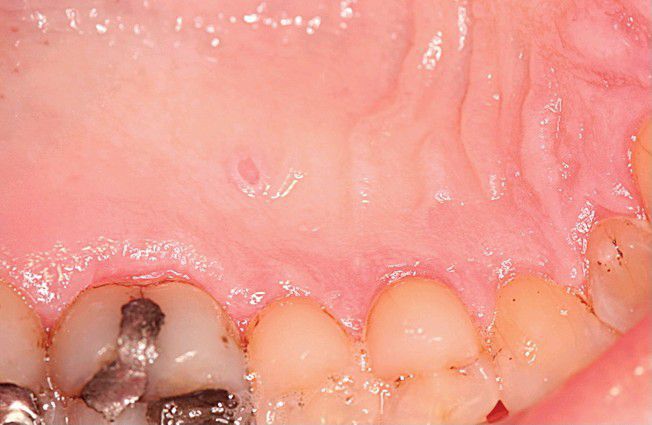

Warty Dyskeratoma.

Umbilicated papule on the hard palate.

Palate

Warty

Dyskeratoma